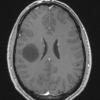

NEOPLASMS (GLIAL)

Astrocytoma, IDH-mutant, WHO Grade 2 (12)